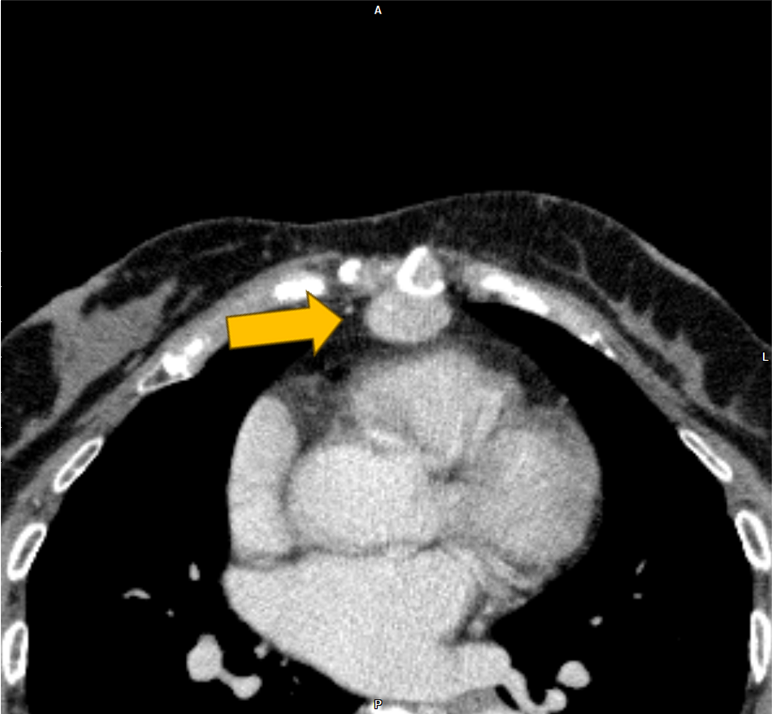

右腎癌(淡明細胞型腎細胞癌)術後の経過観察中に、左腎、膵尾部、胸骨の腫瘍が明らかとなり、胸骨病変の組織診断により右腎癌の転移の確定診断となった。本CTは化学療法中の治療効果判定目的に施行された腎ダイナミック造影CTである。

当該疾患の診断における造影CTの役割

右腎癌術後(淡明細胞型腎細胞癌)、左腎、膵体部、胸骨背側に腫瘤を認める。造影CTにおいての膵実質との増強効果の違いにより膵腫瘍を描出することができる。膵腫瘤はDynamic造影で早期濃染色、washoutパターンを呈しており、乏血性の造影パターンを呈す通常の膵癌との鑑別は容易である。